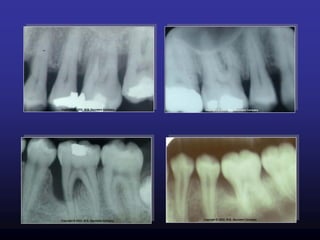

Radiographic

Examination

• Horizontal

• Angular

Bone loss

 Write tooth numbers.

 Place a black dot in furcation on the dental charting

(See Key for Chart)

Furcation Involvement

(radiolucency between

roots)

Lamina Dura